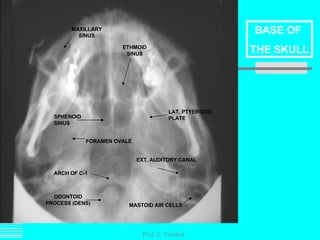

Prof. Z. Vinokur ODONTOID PROCESS (DENS) ETHMOID SINUS SPHENOID SINUS MAXILLARY SINUS LAT. PTYERGOID PLATE FORAMEN OVALE ARCH OF C-1 EXT. AUDITORY CANAL MASTOID AIR CELLS BASE OF  THE SKULL

Prof. Z. VinokurODONTOID PROCESS (DENS) ETHMOID SINUS SPHENOID SINUS MAXILLARY SINUS LAT. PTYERGOID PLATE FORAMEN OVALE ARCH OF C-1 EXT. AUDITORY CANAL MASTOID AIR CELLS BASE OF THE SKULL